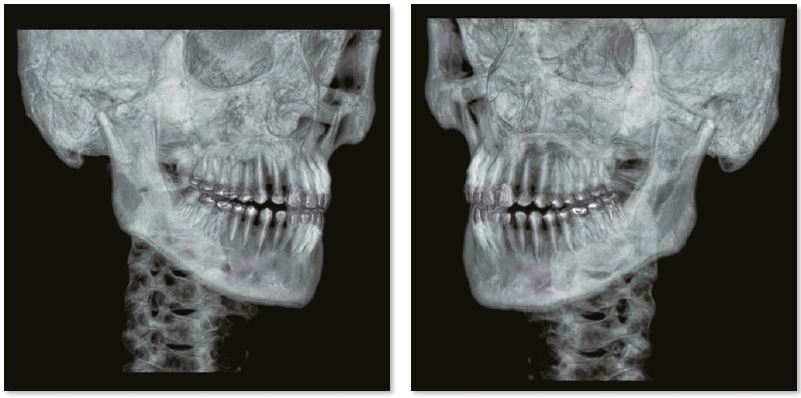

Усунення артефактів від зубних пломб

Артефакти з амальгамних пломб повністю усуваються за допомогою реконструкції SEMAR, що дозволяє точно оцінити прилеглі м’які тканини. На цьому постконтрастному скануванні кісток обличчя видно невелику пухлину, яка прилягає до нижньої щелепи.

3D зображення нижньої щелепи

Звичайне зображення

Зображення з SEMAR